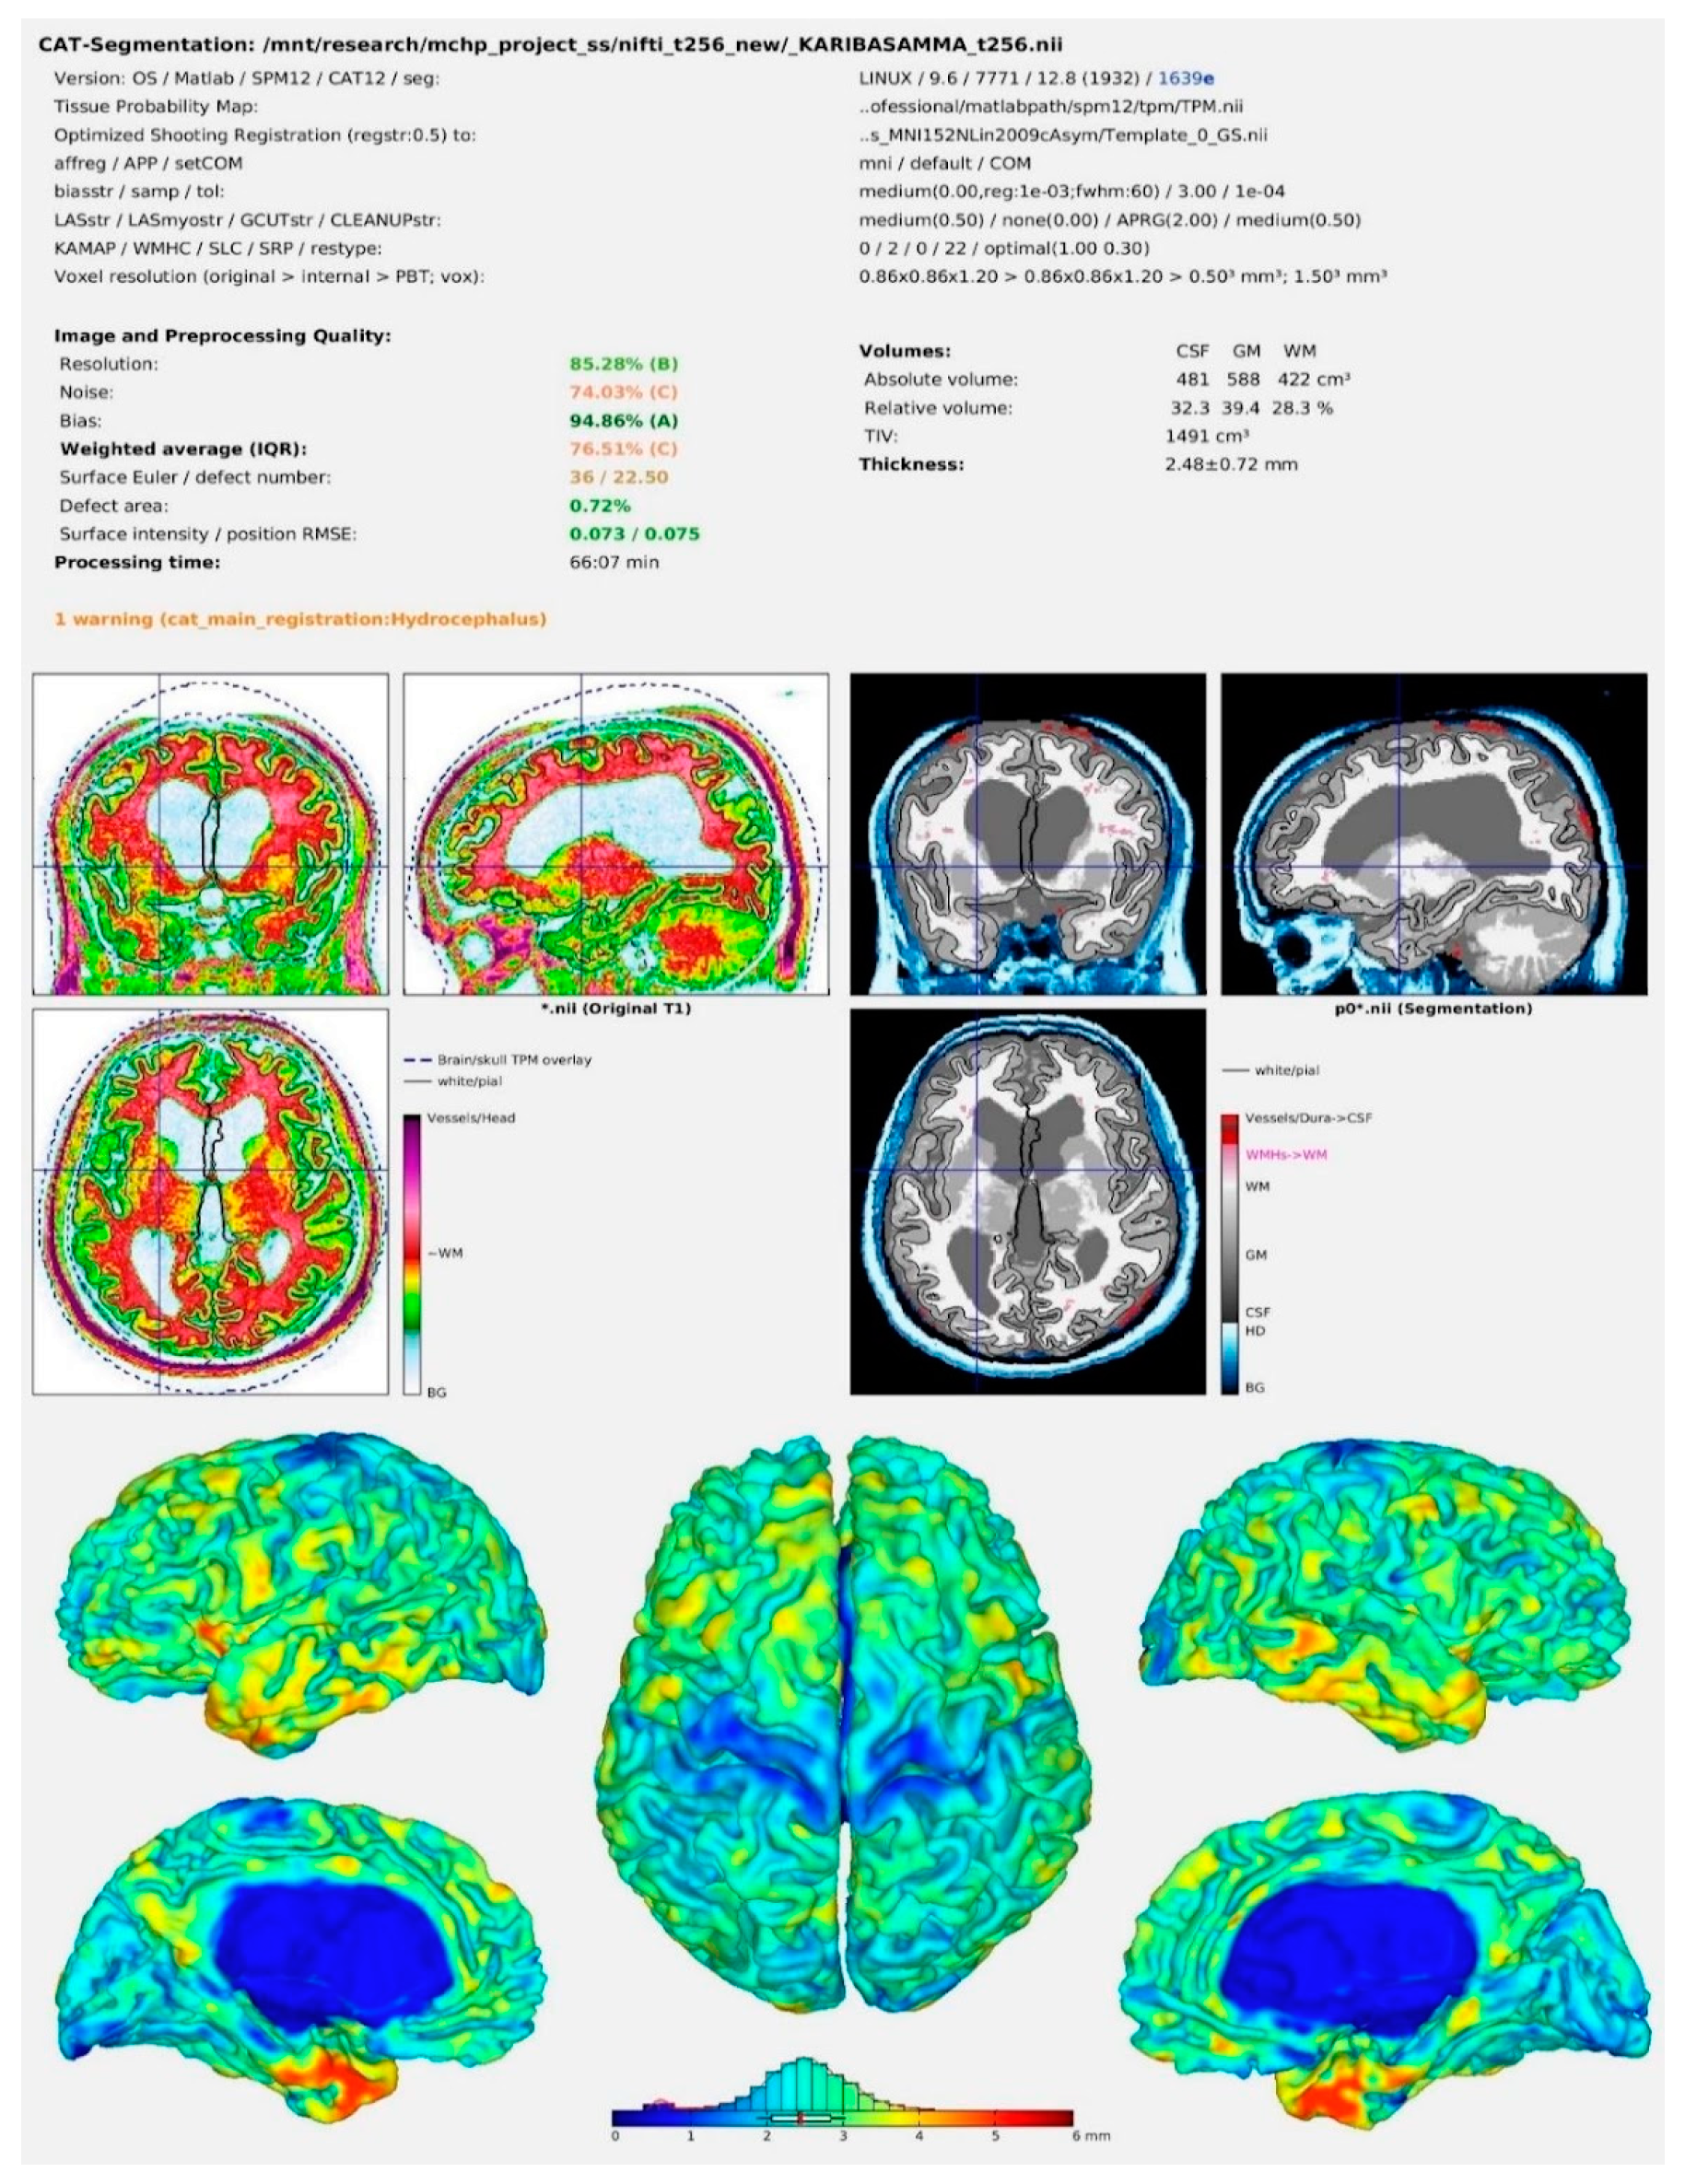

2.5. Image Pre-Processing